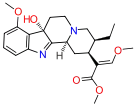

Oripavine derivatives

Thienorphine

- 7-PET

- Acetorphine

- Alletorphine (N-allyl-noretorphine)

- BU-48

- Buprenorphine

- Buprenorphine-3-glucuronide

- Cyprenorphine

- Dihydroetorphine

- Etorphine

- Homprenorphine

- 18,19-Dehydrobuprenorphine (HS-599)

- N-cyclopropylmethylnoretorphine

- Nepenthone

- Norbuprenorphine

- Norbuprenorphine-3-glucuronide

- Thevinone

- Thienorphine

Structures

| Oripavine derivatives | ||||

|---|---|---|---|---|

7-PET 7-PET |

Acetorphine Acetorphine |

Alletorphine Alletorphine |

BU-48 BU-48 |

Buprenorphine Buprenorphine |

Cyprenorphine Cyprenorphine |

Dihydroetorphine Dihydroetorphine |

Etorphine Etorphine |

Homprenorphine Homprenorphine |

18,19-Dehydrobuprenorphine 18,19-Dehydrobuprenorphine |

N-cyclopropylmethylnoretorphine N-cyclopropylmethylnoretorphine |

Nepenthone Nepenthone |

Norbuprenorphine Norbuprenorphine |

Thevinone Thevinone |

Thienorphine Thienorphine |